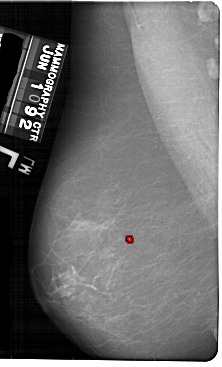

A_1864_1.LEFT_CC

LEFT_CC LINES 5491 PIXELS_PER_LINE 3646 BITS_PER_PIXEL 12 RESOLUTION 43.5 OVERLAY

FILE: A_1864_1.LEFT_CC.OVERLAY

TOTAL_ABNORMALITIES 1

ABNORMALITY 1

LESION_TYPE CALCIFICATION TYPE PLEOMORPHIC DISTRIBUTION CLUSTERED

ASSESSMENT 4

SUBTLETY 2

PATHOLOGY BENIGN

TOTAL_OUTLINES 1

BOUNDARY